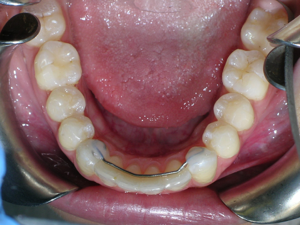

Here are the results. We used a bonded retainer on the bottom teeth.